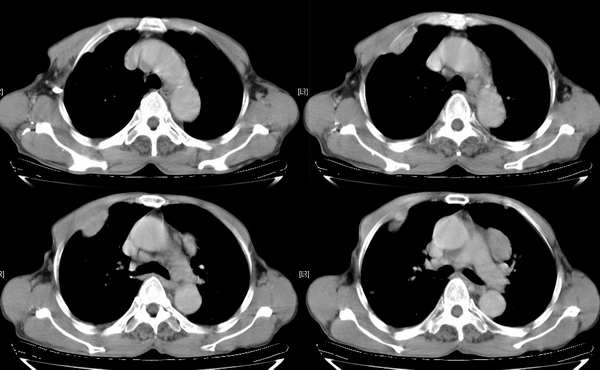

右颈部巨大软组织肿块影,范围较广,上至下颌角,下至颈静脉切迹。其最大层面位于右侧甲状腺区。肿块密度不均,其中有坏死液化区和班片状钙影,增强扫描见肿块实质区有强化。邻近结构挤压移位,部分结构侵蚀破坏,右侧多个颈深淋巴结肿大。两肺弥漫分布小结节影,以胸膜下为主,其大小不等,边缘光整。右侧胸壁亦见软组织结节影,纵隔多个淋巴结肿大及两侧锁骨上淋巴结肿大。

意见:右侧甲状腺癌并两肺、胸壁、纵隔淋巴结、颈深淋巴结、锁骨上淋巴结等广泛转移。

右侧甲状腺腺癌伴颈部纵隔淋巴结转移、纵隔淋巴结转移、肺内多发转移及胸膜转移。

右侧甲状腺癌伴两肺多发转移、纵隔淋巴结转移及胸膜转移